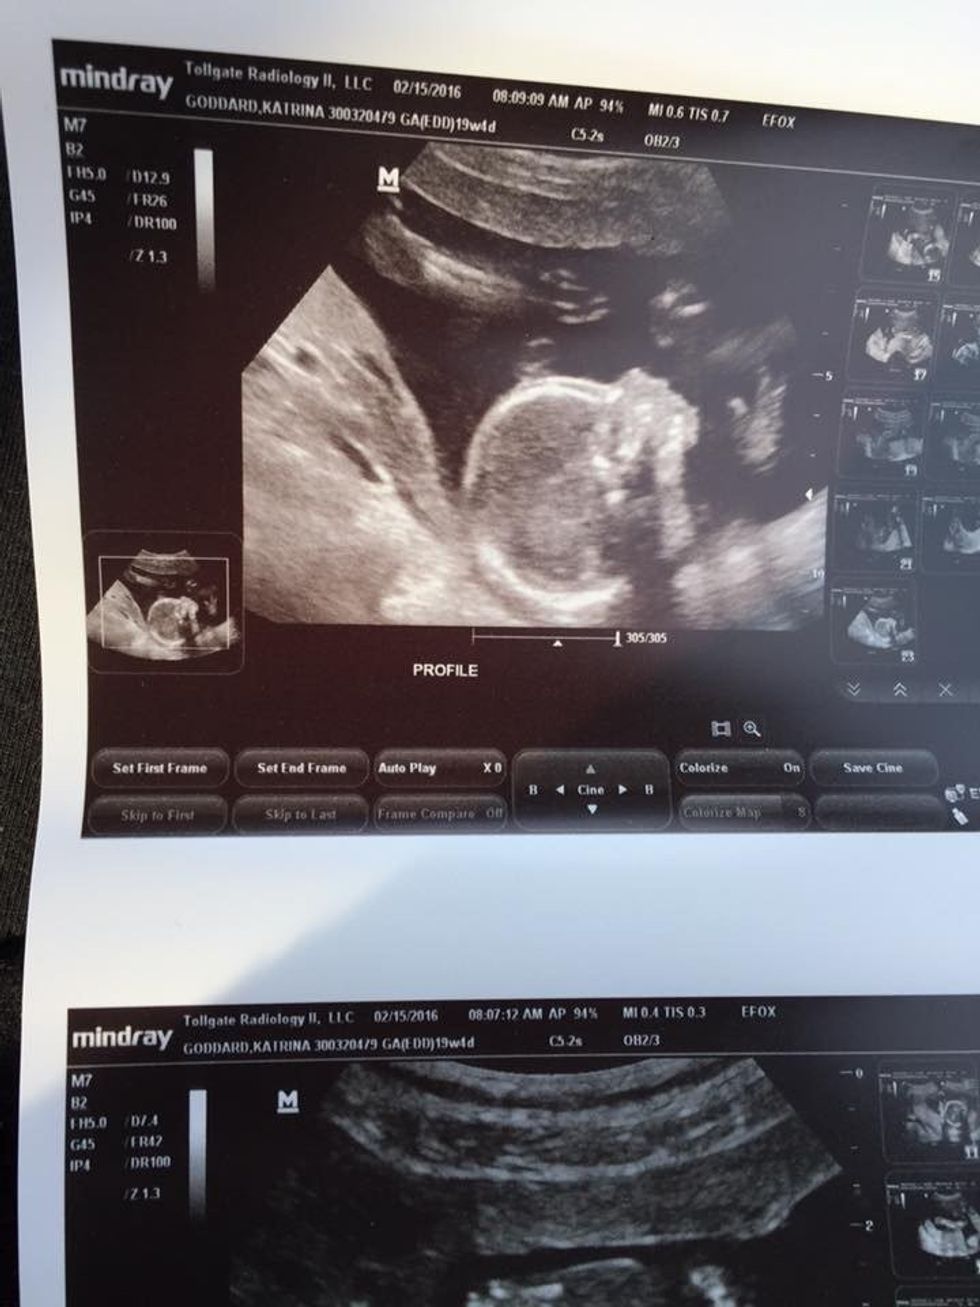

At first, it was hard. Morning sickness made it so the last thing I wanted to do was eat and it still hadn't sunk into my head that I was really pregnant. It wasn't until I got my first ultrasound that it truly hit me and whenever I had a hard time coping, I would look at that ultrasound and remember who I was doing this for. I pushed past the never-ending nausea and I ate even the smallest foods just so my baby would get something.